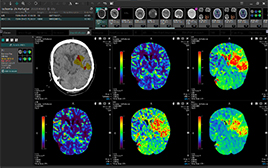

Brain Perfusion |

・Brain Perfusion

・MR Diffusion Perfusion Mismatch